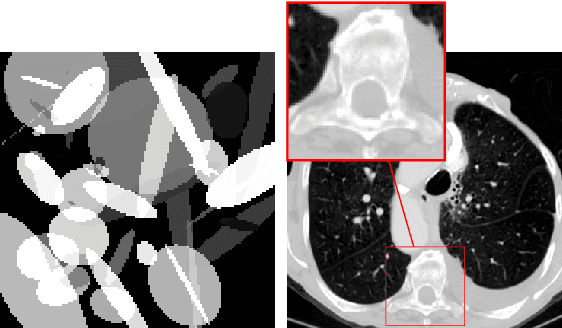

Abstract:Deep learning-based image reconstruction approaches have demonstrated impressive empirical performance in many imaging modalities. These approaches generally require a large amount of high-quality training data, which is often not available. To circumvent this issue, we develop a novel unsupervised knowledge-transfer paradigm for learned iterative reconstruction within a Bayesian framework. The proposed approach learns an iterative reconstruction network in two phases. The first phase trains a reconstruction network with a set of ordered pairs comprising of ground truth images and measurement data. The second phase fine-tunes the pretrained network to the measurement data without supervision. Furthermore, the framework delivers uncertainty information over the reconstructed image. We present extensive experimental results on low-dose and sparse-view computed tomography, showing that the proposed framework significantly improves reconstruction quality not only visually, but also quantitatively in terms of PSNR and SSIM, and is competitive with several state-of-the-art supervised and unsupervised reconstruction techniques.